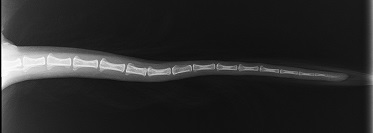

Patella

04.06.2024

re-0, li-1